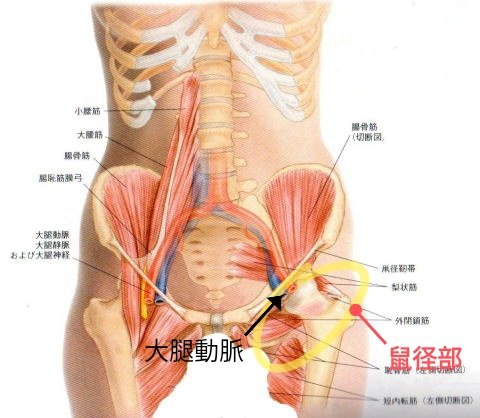

左足鼠径部を前の病院で手術したのですが瘢痕組織(傷が硬く成った組織)が大きく取れて居なかった為今回の手術を行ったのですが手術内容は左の広背筋と血管を取ってきて鼠径部に入れて血管を繋げ筋肉の働き良くし肉も血が通った肉にしてあげる って内容でした。が広背筋の切除は終わり (続く